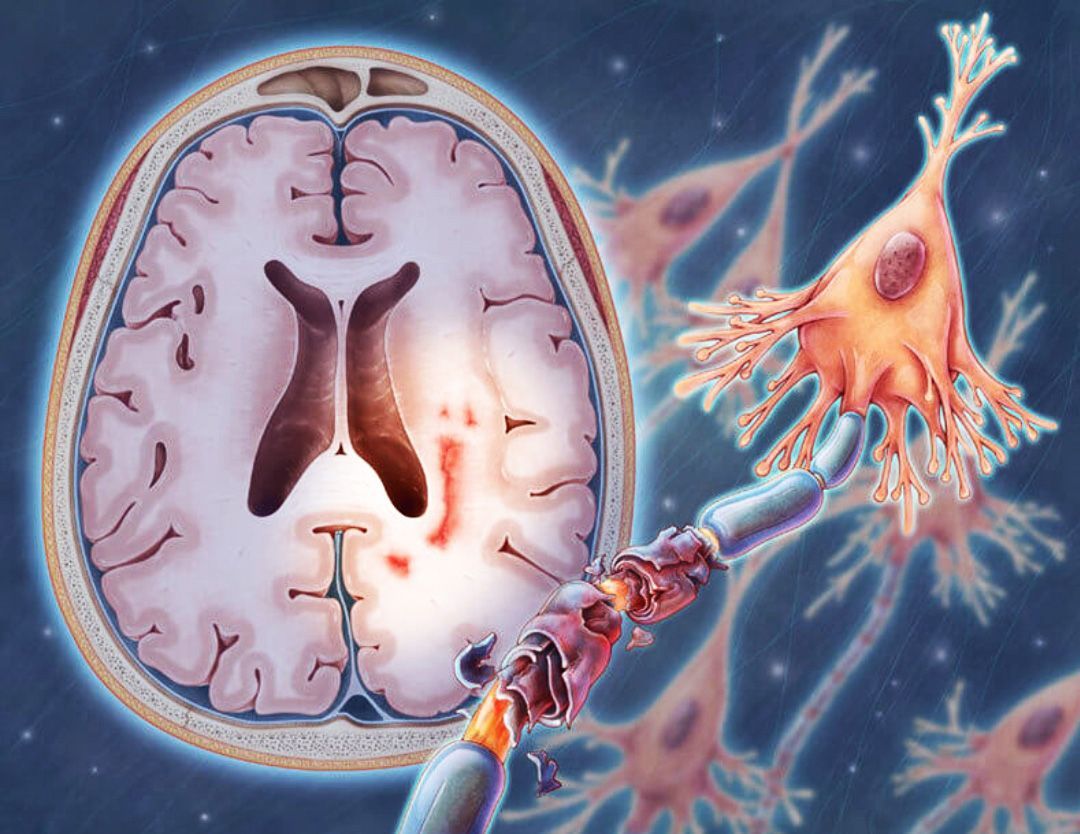

Хроническая ишемия головного мозга и лейкоареоз: симптомы и лечение